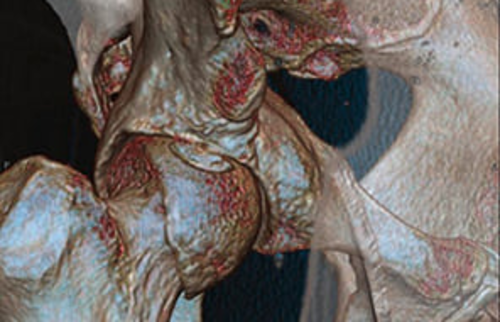

Eine 3D-Rekonstruktion einer Computertomographie (CT) eines Hüftgelenks.

Abbildung 1.